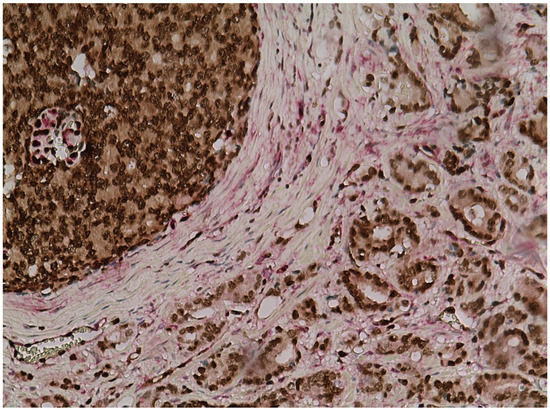

3.1. ERG and PTEN Associations in Prostate Carcinoma

3.2. Association of ERG Expression with Gleason Grade Pattern in Prostate Cancer

3.5. AMACR Expression in Prostate Cancer and Its Association with PTEN